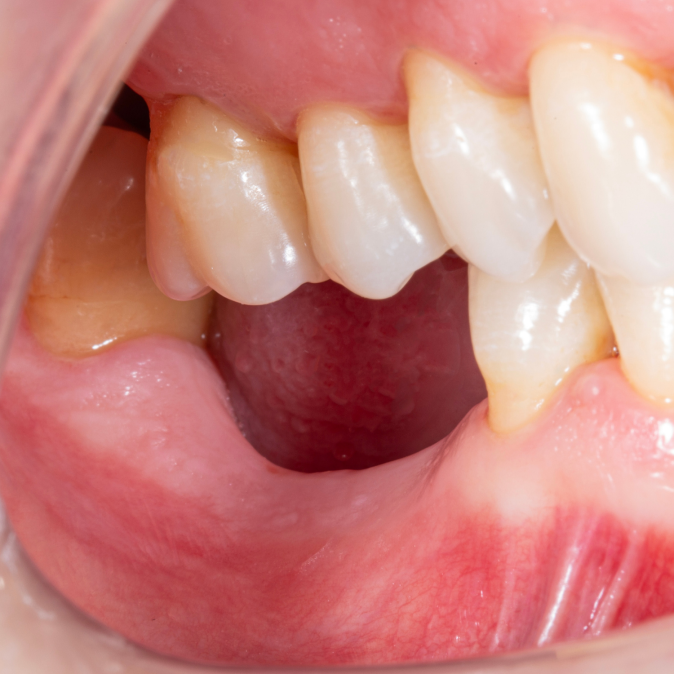

Diş çekiminin yıllar önce yapılmış olmasına bağlı olarak ince kemik varlığında implant ve kemik grefti uygulandı.